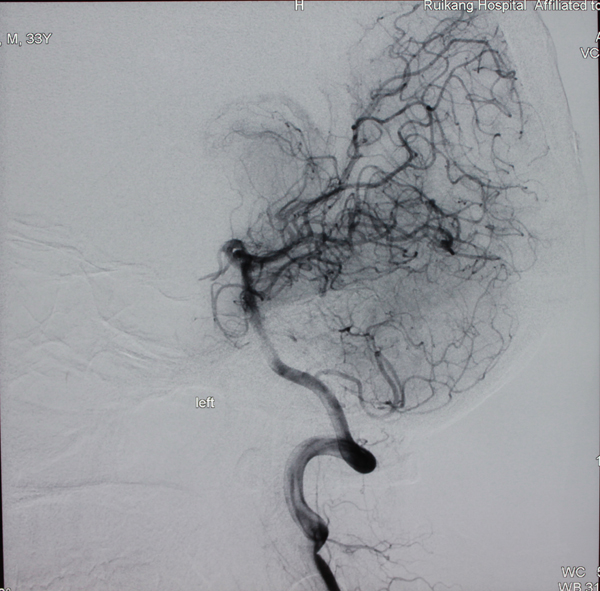

由于没有明显外伤,神经外科主治医师李亚平对病情进行分析后判断,李明很有可能是动静脉畸形导致的脑出血,从而引起头痛头晕,失去知觉。在明确病因后,李医生通过开颅手术将动静脉畸形进行切除,挽救了李明的生命。

对于动静脉畸形的治疗,主治医师李亚平介绍,有三种方式:开颅切除手术、介入治疗和放射治疗。开颅手术效果最彻底,能够将动脉畸形根除,是治疗动静脉畸形的最理想方式,但对于位于功能区的畸形和不适宜手术治疗的患者可采取放射治疗或介入治疗,同样能够起到良好的效果。“神经外科医生会根据动静脉畸形在大脑中所处的位置及病人的发病情况来选择最适合的治疗方案。”

手术后